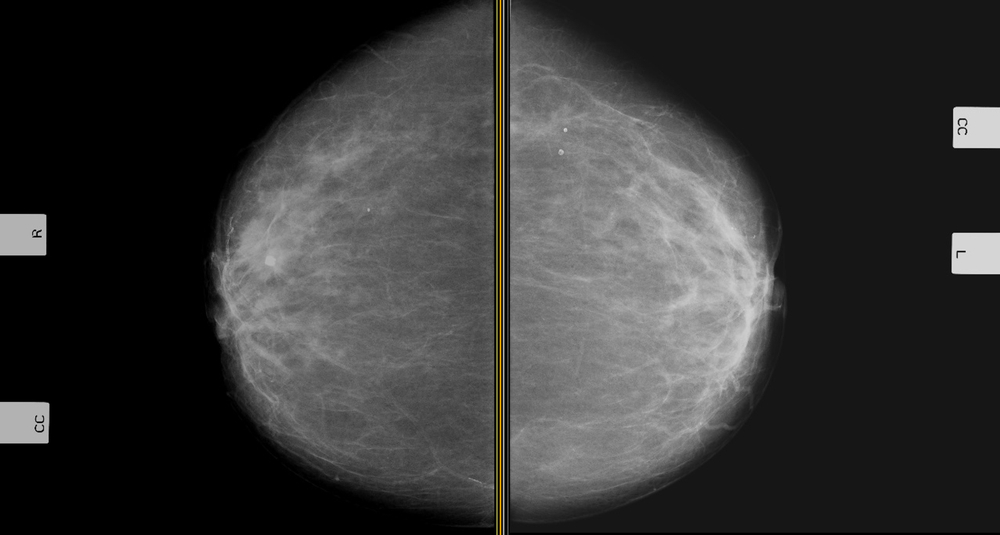

Diagnosing breast cancer

When breast cancer is suspected, different cancer markers can be used. They cannot make a diagnosis on their own. They include: